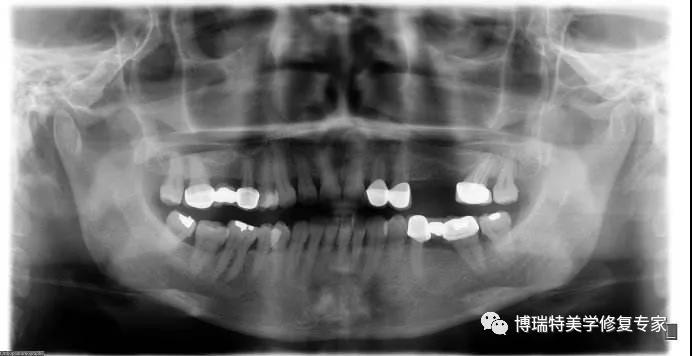

在软组织切开的过程中常可出现出血,黏骨膜剥离损伤大、黏膜下剥离广泛、术后压迫不良、钻孑L过深伤及-l齿槽血管、颌骨内肿瘤破裂等是发生出血的常见原因。如受全身因素影响如患者患有出血性倾向疾病时,手术时也可发生出血。术中出血除造成出血过多外,若血液倒流人口底,还可能阻塞呼吸,导致窒息。为了避免术中出血,种植手术时应尽量减小创伤,术前应拍摄X线曲面断层片,了解下颌管的位置及走行,设计好种植体的植入深度及植入方向,避免损伤下牙槽血管。

为了避免上颌窦穿通,种植牙手术前应拍摄X线片,并以此为依据选择好适当的种植体,确定植入深度。若上颌窦位置过低时,可行上颌窦提升术,后再植入种植体。在某种情况下还可以避开上颌窦行冀上颌区种植。小的穿孔不需特殊处理,可在穿孔处放置明胶海绵以封闭穿通口,较大的穿孔较易引起种植体周围炎,需进行黏膜修补后再植人种植体,对于出血严重的病例,还应行上颌窦开窗术,止血后封闭窦底穿孔。

对下牙槽神经或颏神经的牵拉而导致的神经功能障碍,症状一般会逐渐减轻,通常在6个月内可完全恢复。若为种植体末端压迫所导致的神经功能障碍,在摄片并排除其他病因后,应立即取出种植体。另外神经走行路径中的肿瘤压迫也会导致相应的神经功能障碍,此时应及时诊断,对症处理。对于种植术所导致的神经损伤,4~6个月内未进行及时处理会导致神经功能的退化,因此应进行早期处理,在神经损伤一个月内进行。为防止术后神经功能障碍,术前应拍摄X线全景片,对颌骨的高度进行精确的测量,选择合适的种植体,确定种植体植入深度,种植体末端距下颌神经管2 mm距离为安全距离。